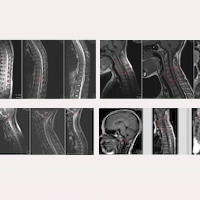

Rys. 1. Przypadek nr 19475: Badania rezonansu magnetycznego z końca 2017 roku – obrazy głowy, odcinka szyjnego, piersiowego i lędźwiowo-krzyżowego.

Na obrazach rezonansu z 2017 roku (Rys. 1) widoczne były m.in.:

- Obniżenie migdałków móżdżku do poziomu między dolną krawędzią C1 a górną C2. Lekkie poszerzenie IV komory.

- Szeroka jama syringomieliczna w odcinku C4–D1.

- Obrzęk niedokrwienny w odcinku szyjnym i piersiowym sięgający aż do stożka rdzenia (stan przed-syringomieliczny).